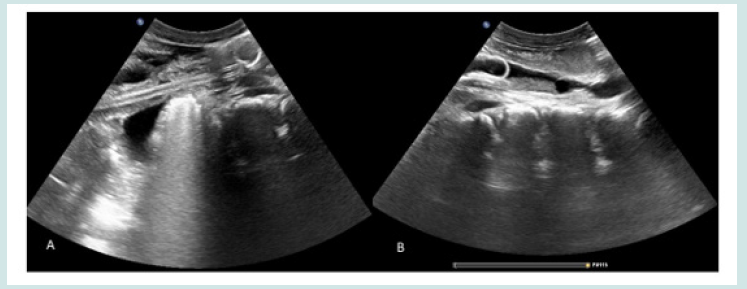

USG abdomen showed absent right kidney with normal size left kidney with moderate hydronephrosis and hydroureter. Her urinary bladder was empty with absence of foley’s catheter balloon in ultrasound (Figure 1). Inflated Foley’s catheter balloon was visualized in dilated left upper ureter 5 cm distal to pelvic ureteric junction. Isoechoic debris is also noted in left upper ureter (Figure 2). The malpositioned foley’s balloon was subsequently urgently removed by pediatric nephrologist simply by pulling back after balloon deflation without any immediate complication. Shortly following the procedure, the patient’s oliguria resolved to some extent. A follow up ultrasound showed persistent hydronephrosis and hydroureter in left kidney possibly due to poorly functioning solitary kidney.

Figure 1: Ultrasound image (A) minimal distention of urinary bladder with absent foley’s catheter balloon (B) Moderate hydronephrosis in left kidney.